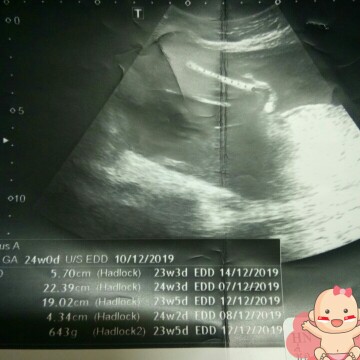

24 สัปดาห์ น้ำหนัก643g. แล้วความยาวดูตรงไหนค่ะ แล้วคำนวนยังไงอยากรู้ว่าตามเกณฑ์หรือเปล่าน่ะค่ะ..

ดูว่าความยาวและน้ำหนักตามเกณฑ์หรือไม่ตามตารางนี้เลยค่ะคุณแม่